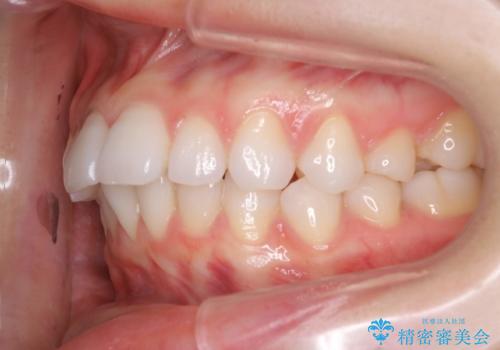

インビザラインで出っ歯を改善する 抜歯をしないinvisalign治療

- 非抜歯・遠心移動による前突の改善をマウスピースにて計画した。

非抜歯矯正の場合、大きく前歯を下げることはできませんが、奥歯の遠心移動や歯のサイズダウンにより歯軸を立て、見かけ上の出っ歯感をある程度改善することができます。